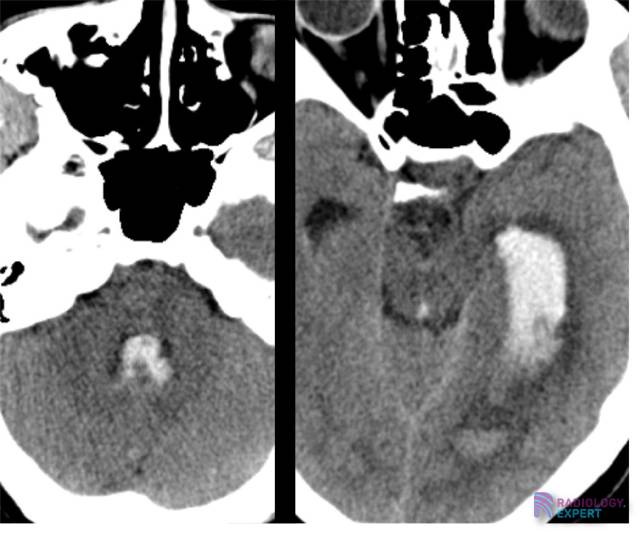

Uitgebreid intraventriculair bloed in de linker laterale ventrikel, het aquaduct en de 4e ventrikel. Uitgebreid intraventriculair bloed in de linker laterale ventrikel, het aquaduct en de 4e ventrikel.

Klik op afbeelding om overlay te zien